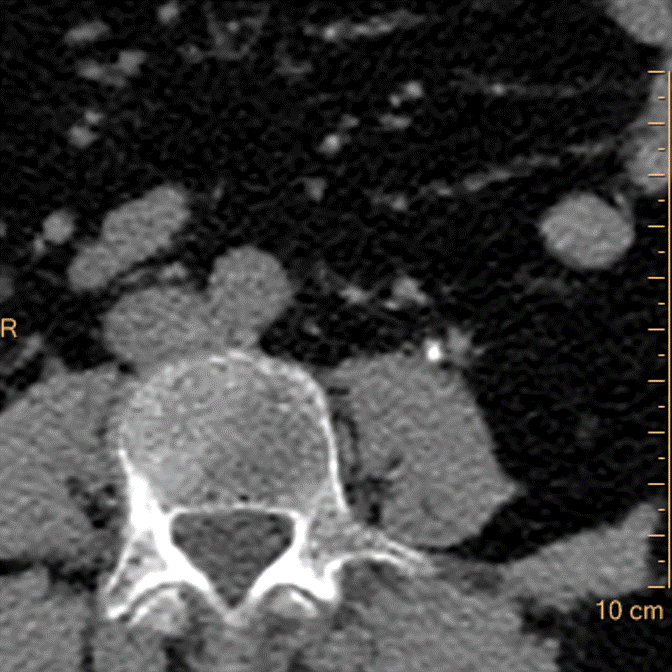

Routine conventional CT shows obstructing stone in left ureter (yellow arrow). There are peripelvic cysts in kidney bilaterally.

conventional CT (axial image). Stone in left ureter (yellow arrow)